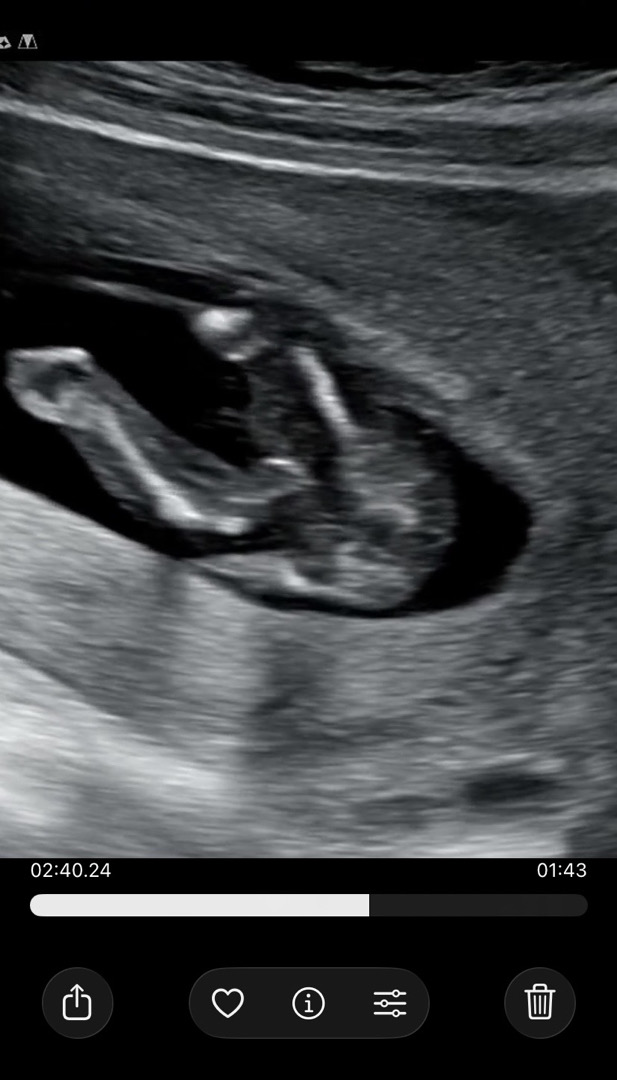

15주 성별봐주세요!!

둘째라서 성별 너무궁금하네요ㅠ 딸?아들? 뭐같아보이시나요?? 3주뒤에 오라는데 ..시간이 안가네요 🥹

사진이 넘 각도가 안좋아서 모르겟네여 ㅠ